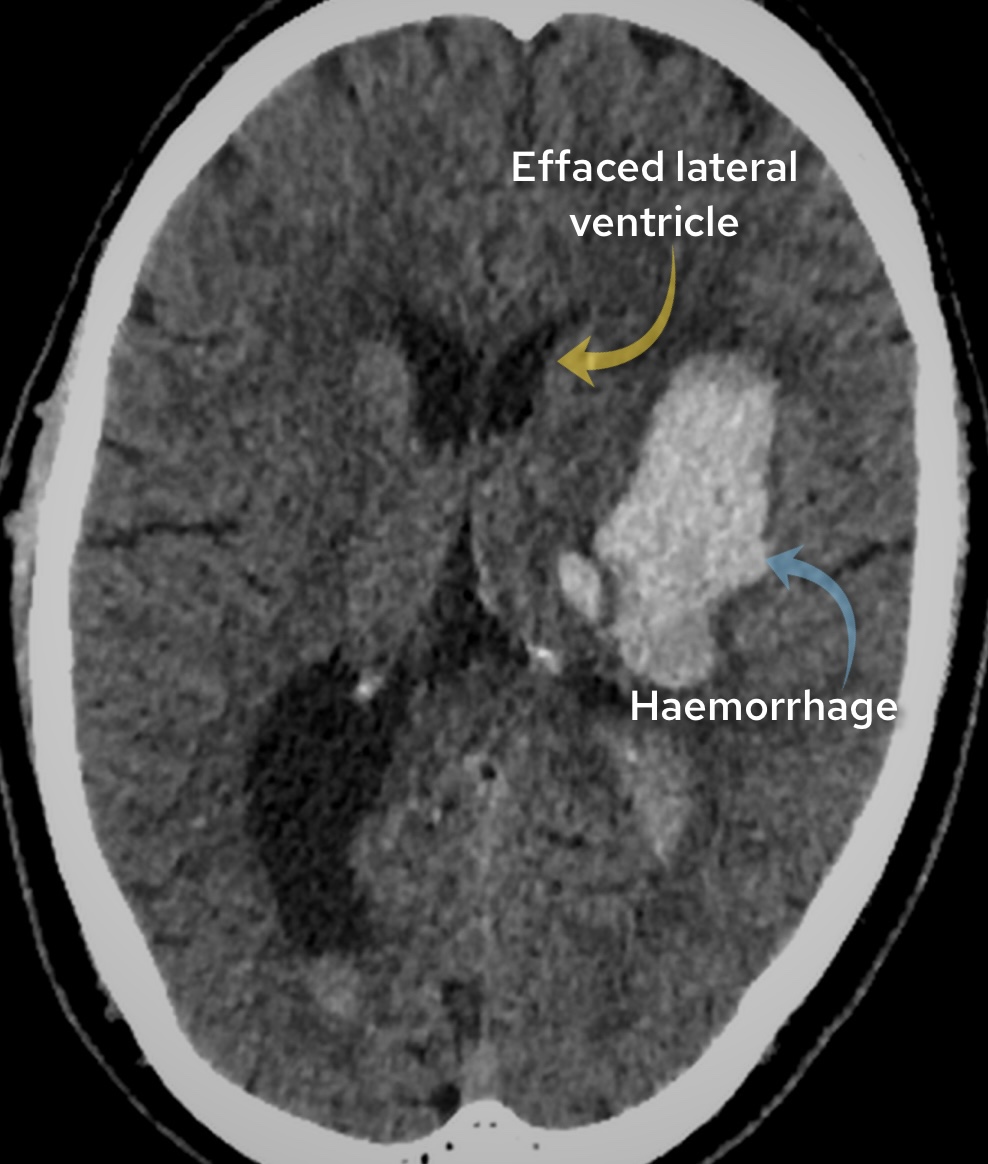

Case 2

A male in his 70s presents with right sided weakness. Have a look at this image from a non contrast CT head. What best describes the finding and most likely diagnosis?

Choose from one of the following options: